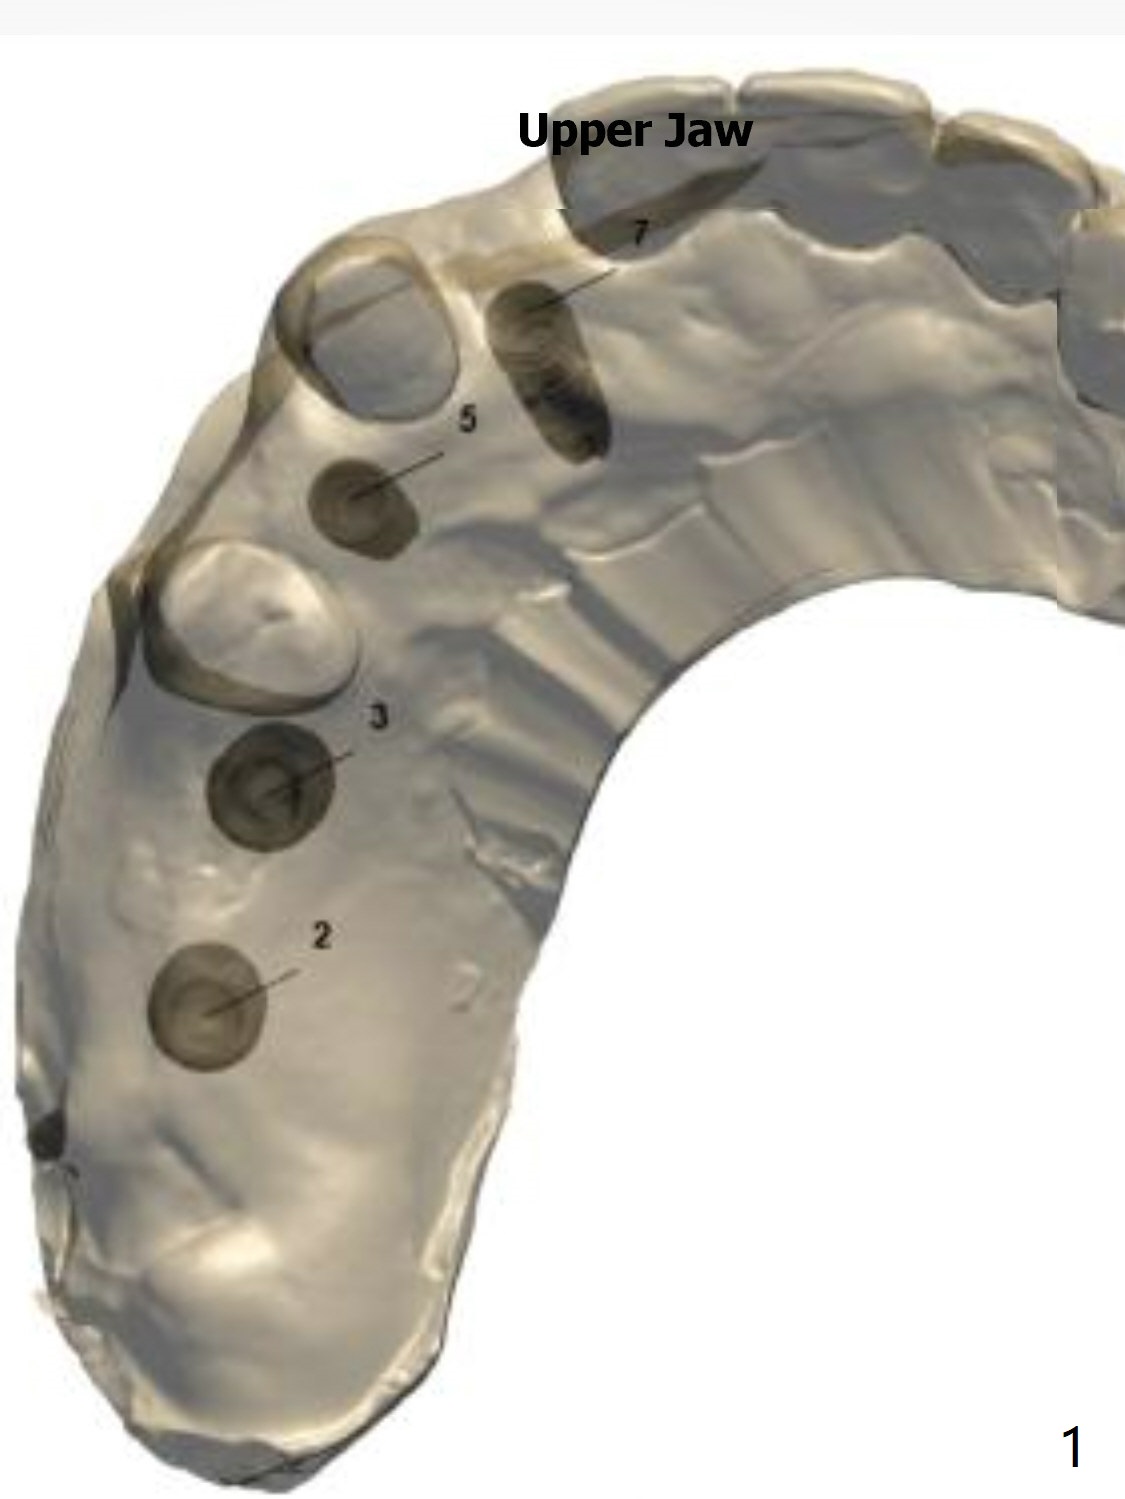

This case requires both narrow and regular navi guide kits and DIO 1-piece implant kit as well as DIO Sinus kits (regular and guided).

Also autoclave DIO guided sinus lift kit and prepare PRF.